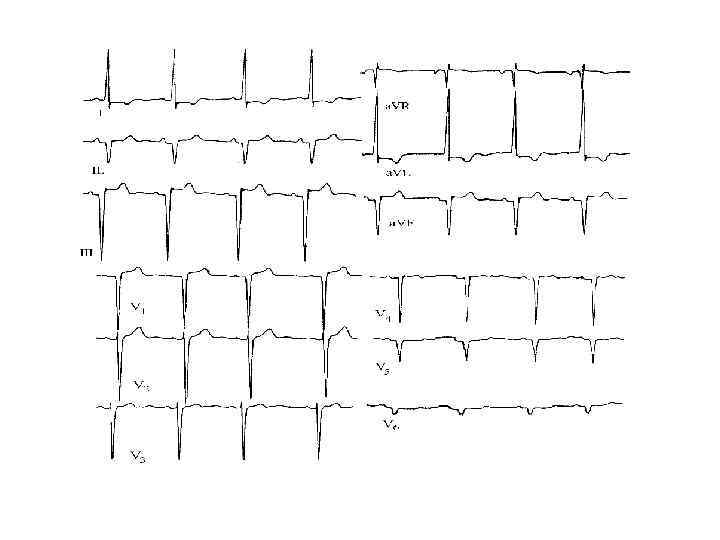

Методы диагностики ЭКГ • нормальная или с неспецифическими изменениями • атриовентрикулярные и внутрижелудочковые блокады • нарушения ритма сердца, МА у 20%

Методы диагностики ЭКГ • нормальная или с неспецифическими изменениями • атриовентрикулярные и внутрижелудочковые блокады • нарушения ритма сердца, МА у 20%

Критерии диагноза АДПЖ III. Нарушения реполяризации Малый Инверсия Т волны в отведениях V 2 и V 3 IV. Нарушения деполяризации/проведения • Большой ü Эпсилон волны или расширение комплекса QRS > 110 мс в отведениях V 1 -V 3 • Малый ü Поздние потенциалы желудочков V. Аритмии Малые ü Желудочковая тахикардия с ЭКГ морфологией БЛНПГ ü Частая желудочковая экстрасистолия > 1000/ 24 часа

Критерии диагноза АДПЖ III. Нарушения реполяризации Малый Инверсия Т волны в отведениях V 2 и V 3 IV. Нарушения деполяризации/проведения • Большой ü Эпсилон волны или расширение комплекса QRS > 110 мс в отведениях V 1 -V 3 • Малый ü Поздние потенциалы желудочков V. Аритмии Малые ü Желудочковая тахикардия с ЭКГ морфологией БЛНПГ ü Частая желудочковая экстрасистолия > 1000/ 24 часа

АДПЖ

АДПЖ